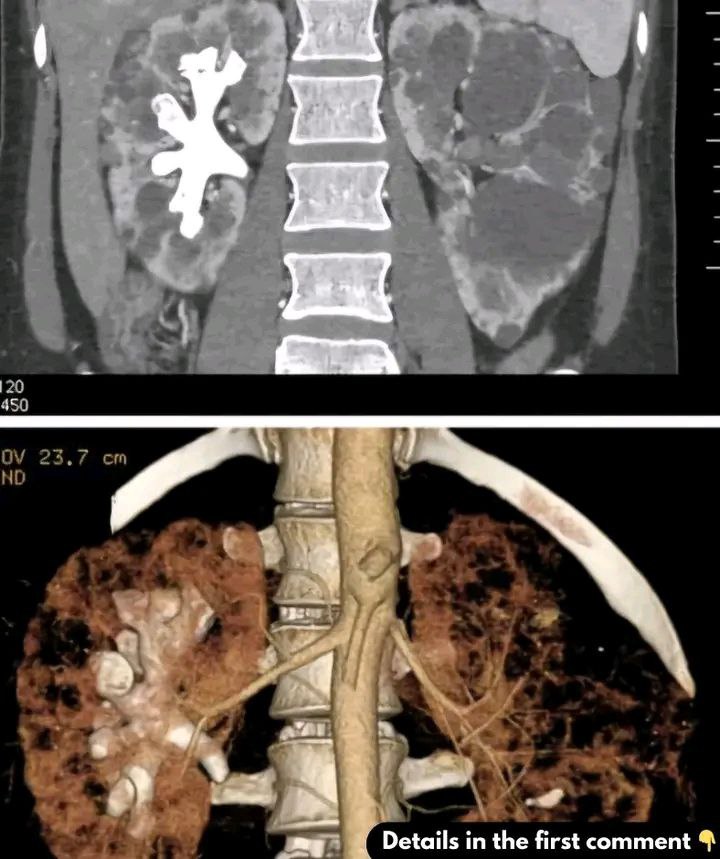

What Are Staghorn Kidney Stones? (Symptoms, Causes, and Treatment)

Staghorn kidney stones are large, complex formations that resemble antlers and can significantly occupy the kidney’s renal pelvis. Typically made of magnesium ammonium phosphate (struvite), these stones often arise from recurrent urinary tract infections (UTIs) and are more common in women. Unlike smaller stones that may pass naturally, staghorn stones usually require surgical intervention due to their size.

Diagnosis typically involves imaging tests like CT scans and urine tests to detect signs of infection. Treatment options include percutaneous nephrolithotomy (PCNL), extracorporeal shock wave lithotripsy (ESWL), and, in rare cases, open surgery. Preventative measures focus on hydration, dietary modifications, and prompt treatment of UTIs. Early intervention is key to maintaining kidney health.